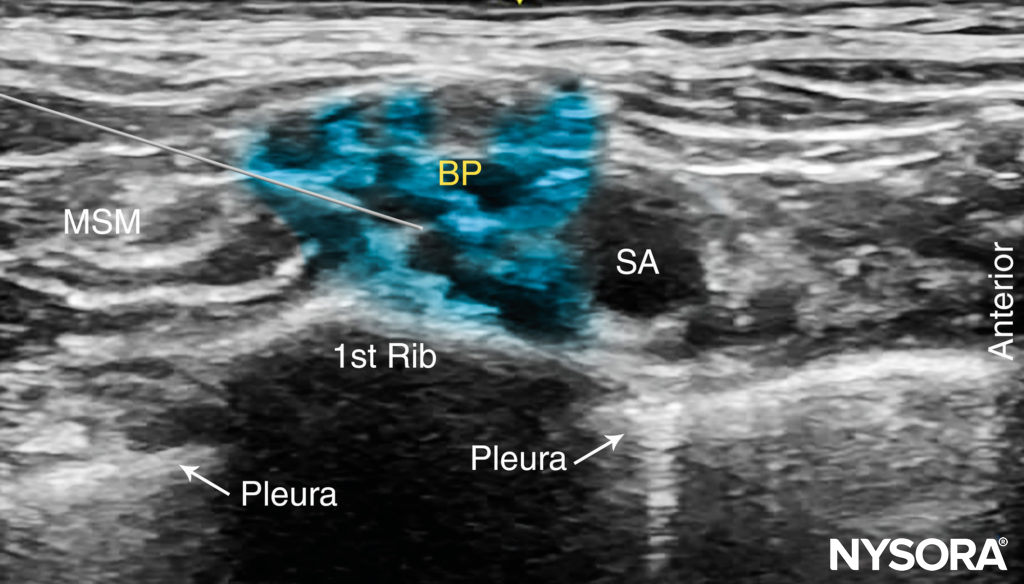

ULTRASOUND ANATOMY

The subclavian artery crosses over the first rib between the insertions of the anterior and middle scalene muscles, posterior to the midpoint of the clavicle. The subclavian artery is readily apparent as an anechoic round structure, whereas the parietal pleura and the first rib can be seen as a linear hyperechoic structure immediately lateral and deep to the subclavian artery (Figure 3). The rib casts an acoustic shadow so that the image field deep to the rib appears anechoic.2 The brachial plexus can be seen as a bundle of hypoechoic round nodules just posterior and superficial to the artery (Figures 3 and 4). It is often possible to see the fascial sheath of the muscles surrounding the brachial plexus. Adjusting the transducer orientation, the upper, middle and lower trunks of the brachial plexus can be individually identified, as they join together at the costoclavicular space. To visualize the lower trunk, the transducer is oriented in the sagittal plane, until the first rib is seen deep to the plexus and the artery. (Figure 4). Anterior or posterior to the first rib is the hyperechoic pleura, with lung tissue deep to it. This structure can be confirmed by observing a “sliding” motion of the viscera pleura in synchrony with the patient’s respiration. The brachial plexus is typically visualized at a 1- to 2-cm depth at this location. The presence of two separate clusters of elements of the brachial plexus may be more or less obvious, sometimes with separation by a blood vessel (Figure 4). The dorsal scapular artery commonly passes through or within the vicinity of the brachial plexus. It is important to recognize that the more superficial and lateral branches come from C5–C7 (shoulder, lateral aspect of arm, and forearm) and can be tracked up to the interscalene area, whereas the deeper and more medial contingent are branches of C8 and T1 (hand and medial aspect of forearm). Adequate spread of local anesthetic in both areas is necessary for successful nerve block of the arm and hand. For additional information see Functional Regional Anesthesia Anatomy.

FIGURE 3. Supraclavicular brachial plexus (BP; yellow arrows) seen slightly superficial and posterolateral to the subclavian artery (SA). The brachial plexus is enveloped by a connective tissue sheath. Note the intimate location of the pleura and lung to the brachial plexus and subclavian artery. MSM, middle scalene muscle.